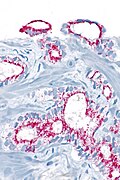

IHC

Usually stains like cancer:

- AMACR +ve.

- CK34betaE12 -ve.

- p63 -ve.

Note:

- Often not contributory.